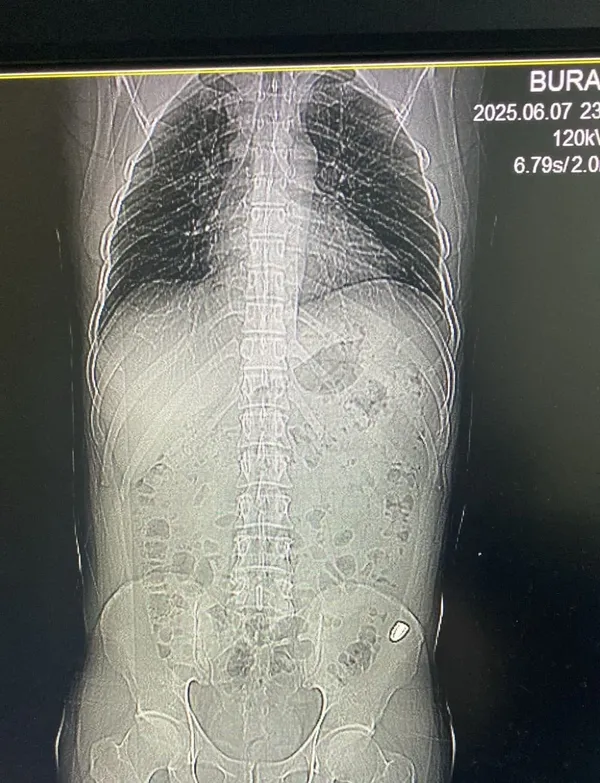

Olay, 7 Haziran akşam saatlerinde Karaisalı ilçesi Topaktaş Mahallesi’ndeki bir hobi bahçesinde gerçekleşti. Ailesiyle piknik yapan Burak Ateş, ani bir karın ağrısı hissetti ve yakınlarından yardım istedi. Yapılan kontrollerde karın bölgesinde kanama olduğu fark edilen Ateş, yakınları tarafından Çukurova Devlet Hastanesi’ne götürüldü. Röntgen sonuçlarında, karnının sol üst bölümüne isabet eden yorgun merminin alt kısma ilerlediği belirlendi. Doktorlar, merminin 13 Haziran’da ameliyatla alınmasına karar verdi ve gerekli müdahalenin ardından Ateş taburcu edildi.